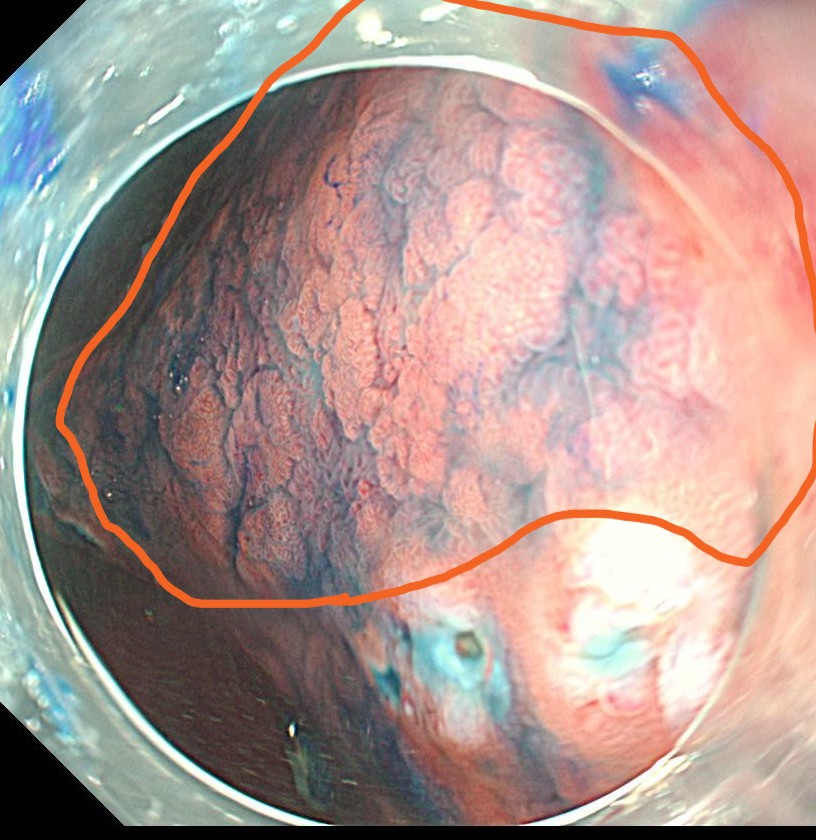

マーキングの外側で全周切開します。フラッシュナイフを用いています。

粘膜下層剥離術を開始します。粘膜下局注はこの症例は生理食塩水とムコアップを使用しました。

オレンジのラインで切除していきます。